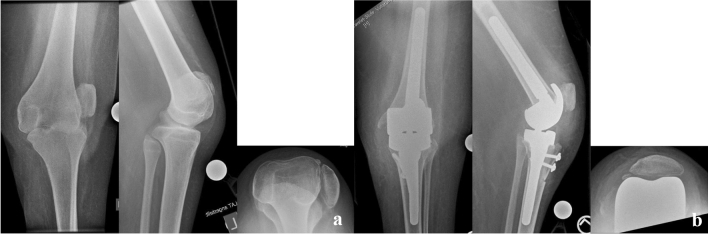

For TKA (exemplary Fig. 2a, b), a medial extensile approach was chosen and concomitant tendon releases were executed. One TKA was performed with a stemmed condylar constrained implant system (Genesis CC, Smith&Nephew Inc., Memphis, TN, USA) and the other with a stemmed rotating hinge knee system due to severe laxity and dysplasia of the femoral condyles (GenuX, Implantcast GmbH, Buxtehude, Germany) which was combined with a tibial tuberosity proximalisation.

Fig. 2.

a Preoperative radiograph of the painful knee in subluxation. b Postoperative radiograph following rotating hinge knee replacement